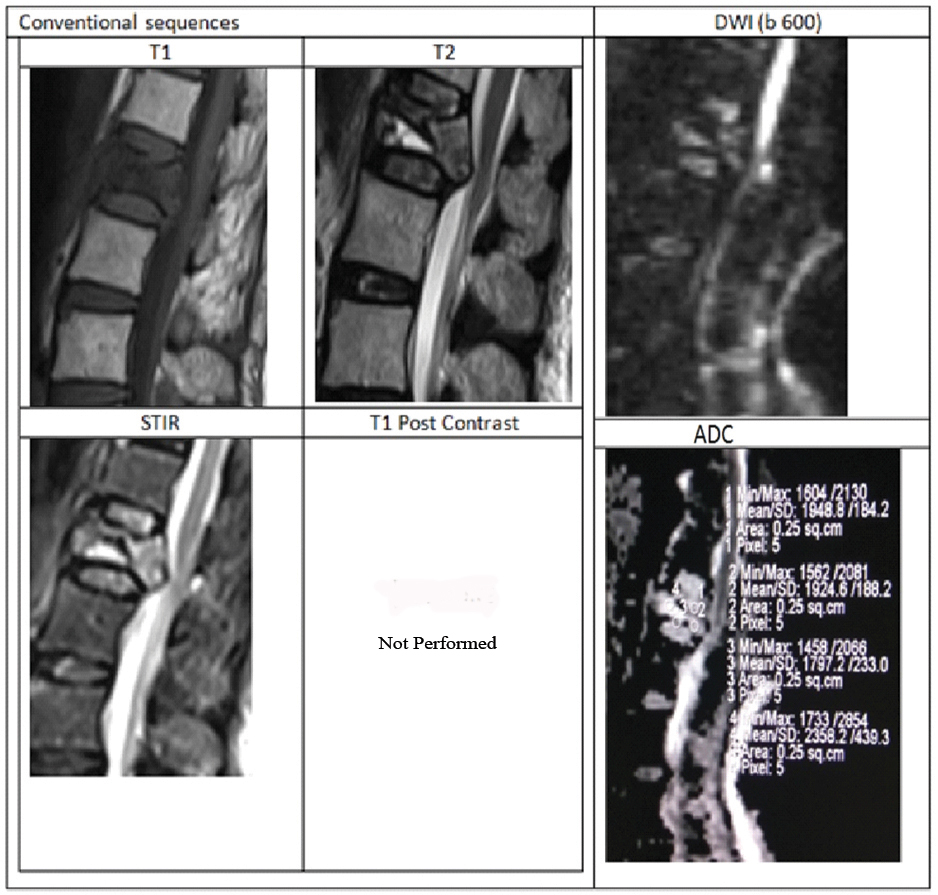

Case of acute osteoporotic compression fracture.

A 78-year-old female presenting with history of trivial fall at house and acute back pain. MRI with DWI showed wedge compression fracture of L1 vertebral body with hypointense marrow signal on T1WI, heterogenous signal on T2WI. STIR images showing hyperintensity with fluid sign (Triangular hyperintensity in the collapsed vertebra). There is retropulsion with posterior convexity in the body of collapsed vertebra compressing the thecal sac and indenting conus medullaris, thus mimicking a malignancy.

DWI showed patchy areas of hyperintense signal but corresponding ADC map reveal no corresponding hypointensity. Mean ADC value in the collapsed vertebra was 1.815×10-3 mm2/sec suggesting benign collapse. Finally, patient underwent surgery to relieve cord compression. HPE analysis from the fracture fragments showed no evidence of malignant cells.